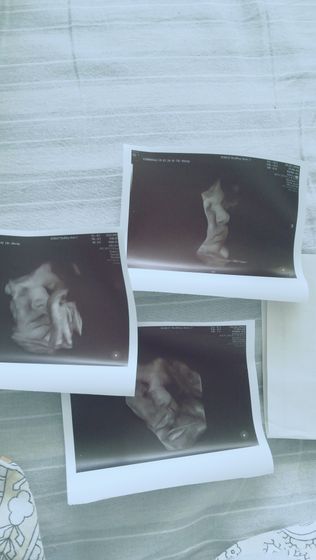

Была сегодня у доктора во 2 роддоме, скзала шейка готовится, щупала долго но не больно, все очень аккуратно ? буду смотреть и наблюдать может все таки запустила мне процесс родов. В пятницу иду на ктг к ним снова, сегодня делали узи и сказали что девочка наша не такая и маленькая 3700 плюс/минус и 57 см, но это мы посмотрим ? даже удалось для папы моську сфотать ?? на 40 то неделе, это удача ??? доча папина, губехи надувает как он у нас во сне ?

а это там же, во 2ом такие снимки сделали?

да, там новый аппарат узи ??

Меня тоже в роддоме смотрели, очень аккуратно, не больно) с утра посмотрели, ночью воды отошли) ну ты знаешь в принципе? а дочь красотка на фото? мне на 38 недели делали фото, какой на снимке вышла — такой и родилась)))

потом можно коллаж сделать в такой же позе, когда спать будет. Снимок прям удачный вышел))

да, я хочу сделать чтобы сравнить ???